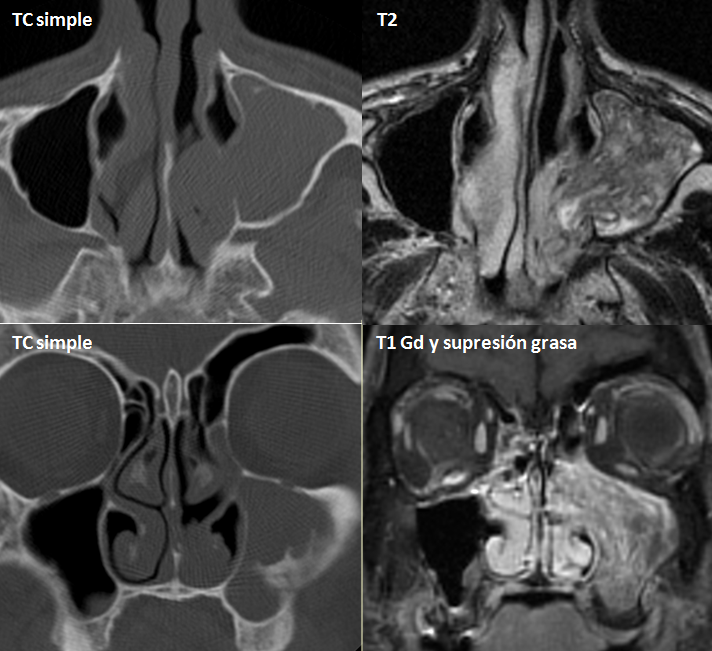

La TC (imagen coronal) muestra un tejido de partes blandas que ocupa el senomaxilar que se acompaña de un fragmento óseo en sumargen lateral (flecha). La RM (secuencia T2) muestraestriacionesestriacioneslineales (patrón cerebriforme) de la masa que ocupa totalmente el senomaxilarizquierdo y que se extiende a la fosa nasal. El estudio anatomopatológico identifica una proliferación celular de patrón endofítico, constituido por células poligonales de núcleo claro.